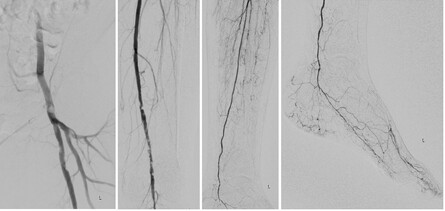

Abb. 2: 2a. Leistenarterien li mit Stenose der AFC li distal, sowie mehreren Abgangsstenosen der AFS; 2b. Mehreren Stenosen der AFS li distal; 2c. Unterschenkelarterien li; 2d. Arterielle Fußversorgung li.